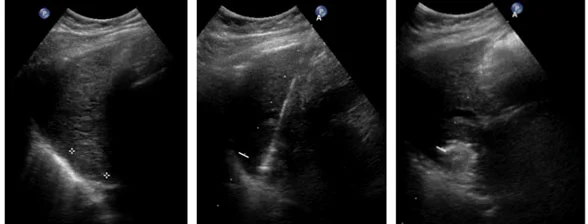

Le microonde sono in grado di ‘bruciare’ masse tumorali di diversi tipi, dimensioni e localizzazione: una sottilissima antenna alloggiata all’interno di un ago viene inserita nel paziente, generalmente sotto guida TAC, ecografica o CBCT; l’antenna brucia il tessuto-bersaglio.

Il campo a microonde sviluppa calore e l’innalzamento locale della temperatura porta alla distruzione della massa tumorale per coagulazione. Questa metodica è ben tollerabile con bassi rischi e minima traumaticità per il paziente.